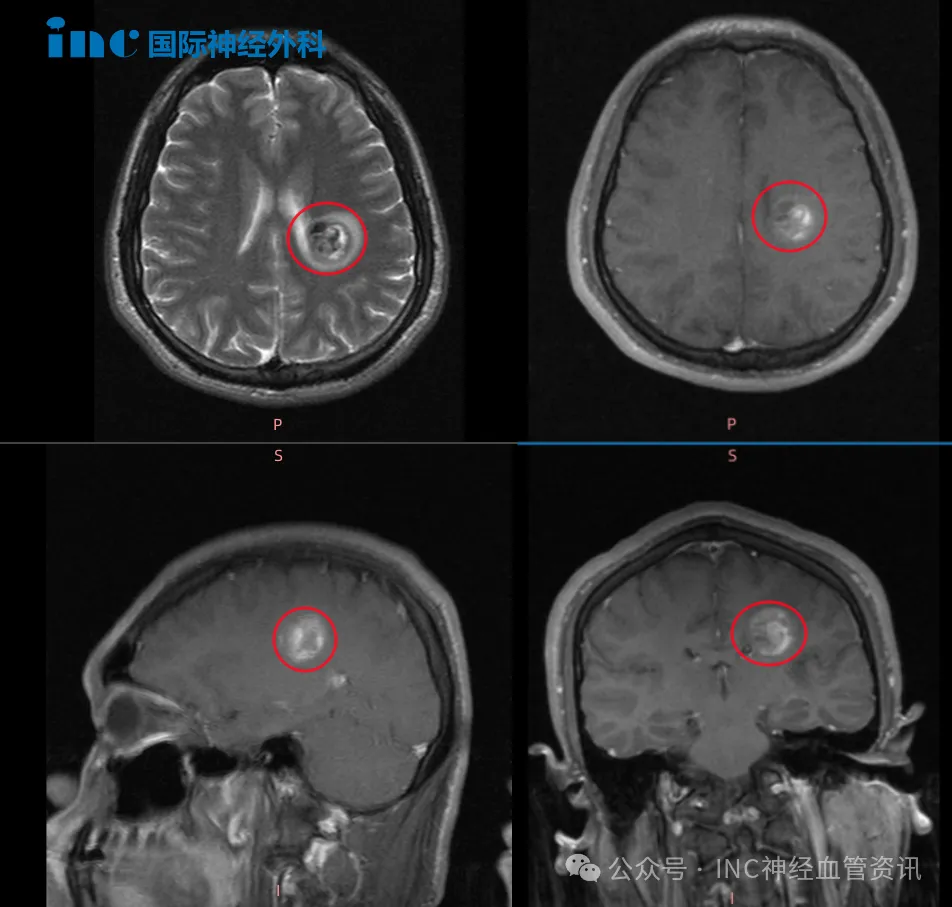

初期误认为复习疲劳,但数日后右腿开始乏力,行走时有踩棉感。随即进行的MRI检查结果显示:左侧半卵圆中心区存在8.0x11.0mm类圆形异常信号灶,诊断为海绵状血管瘤出血。...